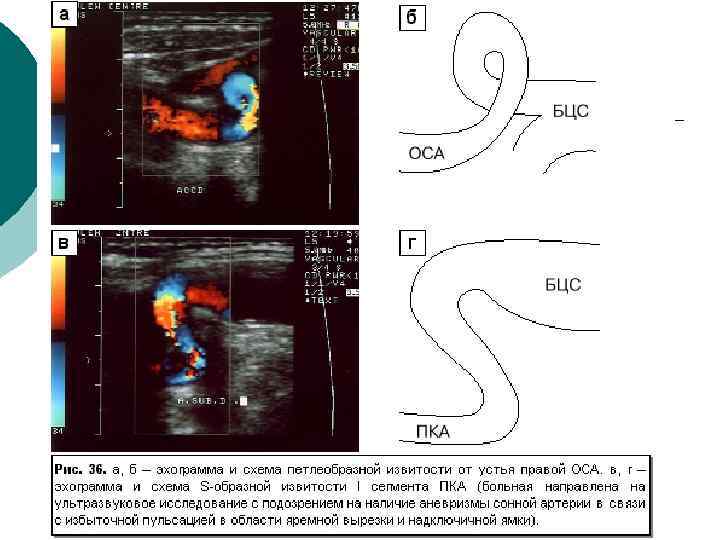

Диагностическая информативность ¡ ¡ ¡ Размеры артерий и вен; Скорости и характер движения крови; Толщина комплекса интима-медия (в норме – до 0, 8 мм в ОСА), наличие бляшек; Наличие извитостей, аневризм и стеноза артерий; Наличие тромбов, перфорантных вен при варикозной болезни, регургитации на клапанах Аномалии развития артерио-венозного русла